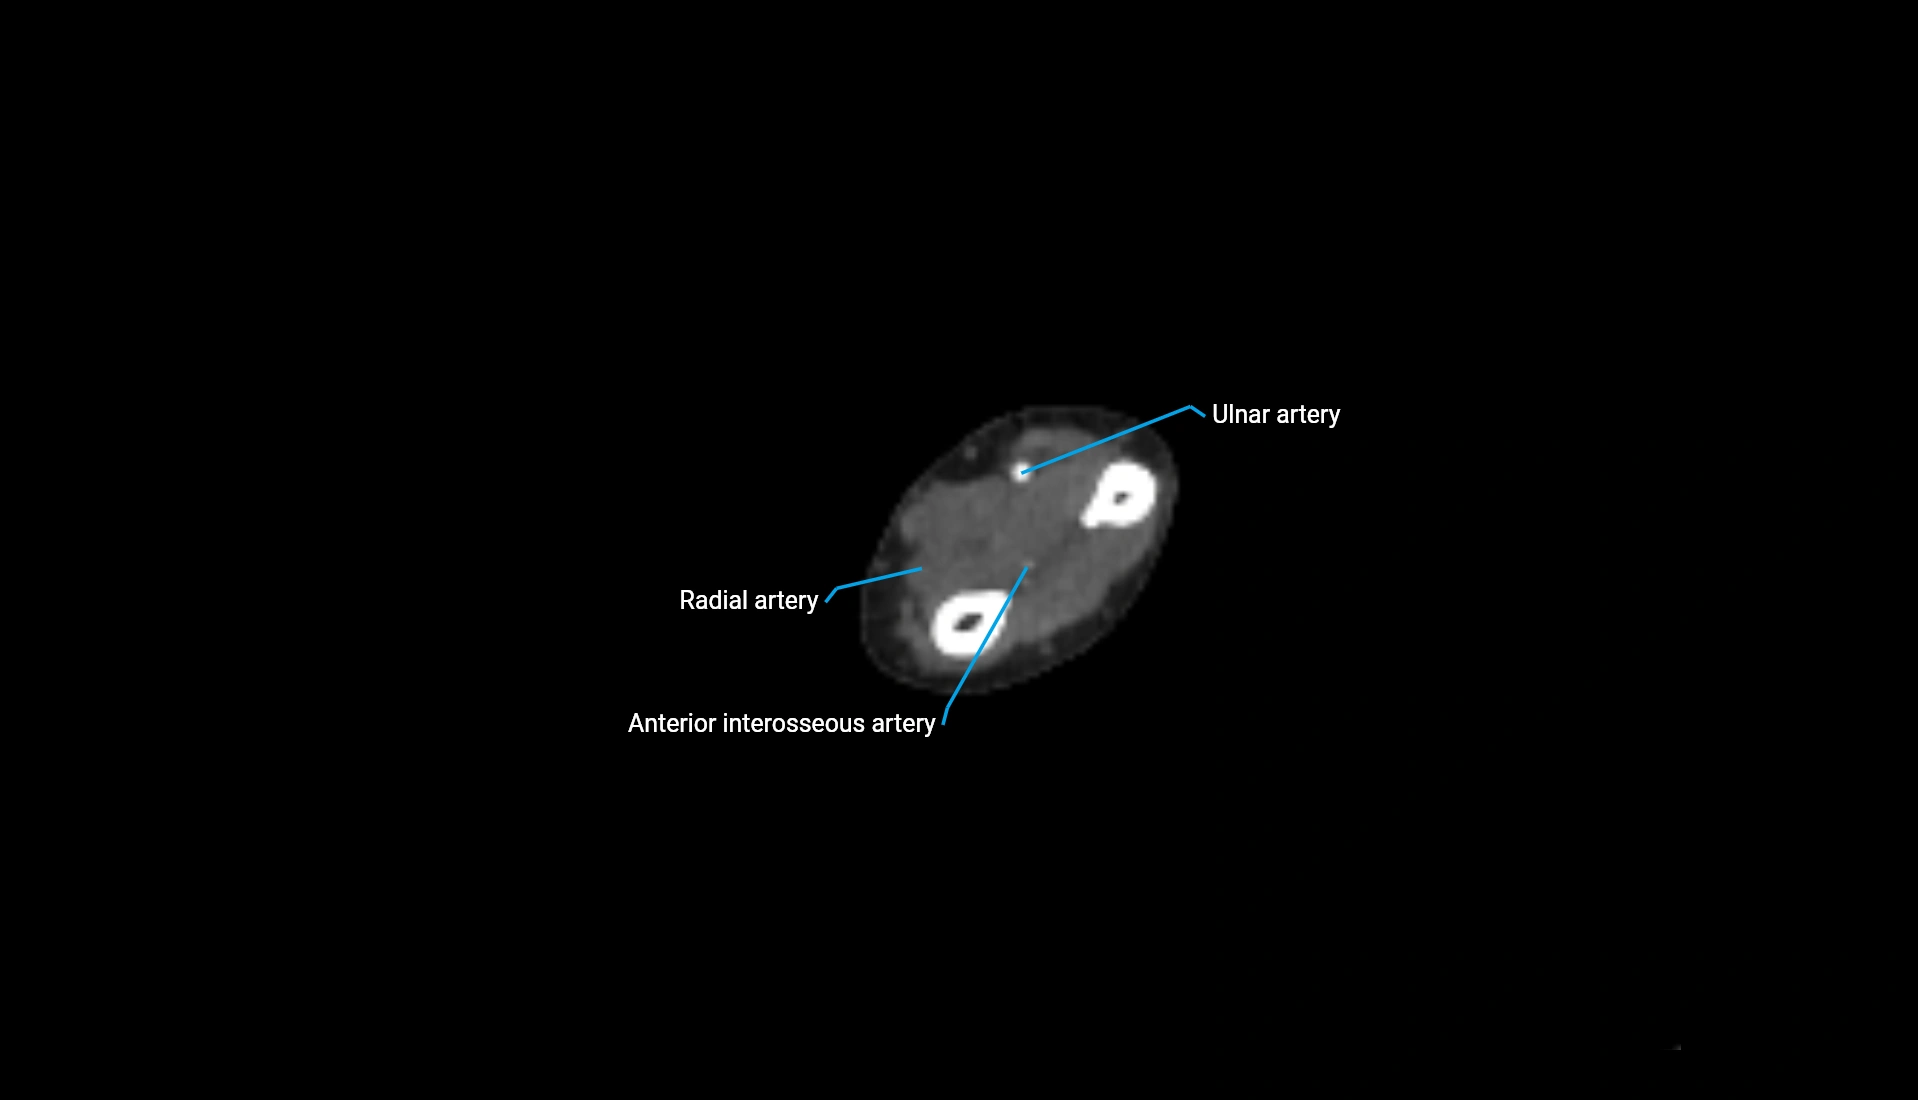

CT Appearance

Non-Contrast CT:

• Cortex: High-density, sharply defined

• Subchondral bone: Dense cancellous matrix

• Articular surface: Smooth concave contour articulating with the capitellum

• Excellent for evaluating bone integrity, alignment, and subtle fractures